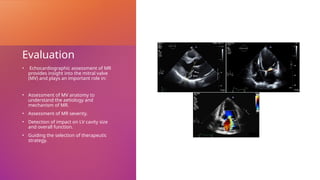

Evaluation

• Echocardiographic assessment of MR

provides insight into the mitral valve

(MV) and plays an important role in:

• Assessment of MV anatomy to

understand the aetiology and

mechanism of MR.

• Assessment of MR severity.

• Detection of impact on LV cavity size

and overall function.

• Guiding the selection of therapeutic

strategy.